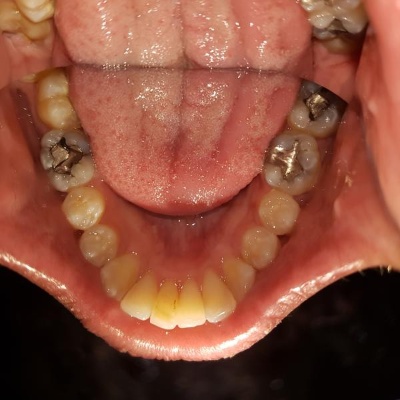

With years of experience in orthodontics, Dr Ghafoor combines expertise in clear aligner systems with comprehensive dental care. He specialises in creating personalised treatment plans that address both aesthetic and functional concerns.